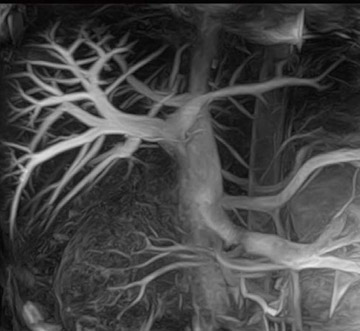

Vantage Titan 3Tは,送信RFコイルへの給電ポイントを4ポイントにし,位相と振幅をコントロールするMulti-phase Transmissionを使用することによって,躯幹部でも濃度ムラのない均一な画像が撮像可能になった(図4)。これにより,3T装置を日常ルーチン検査で躯幹部も含め幅広く使うことが期待できる。3Tのメリットである高いSNRを生かした高分解能撮像が期待できる。さらに,従来は実現困難であった非造影MRAも,躯幹部で使用可能になった(図5)。Time-SLIP法など最新撮像法との組み合わせにより,3Tのポテンシャルを引き出し新しい領域が拓かれるものと期待される。

図5 腹部の非造影MRA(門脈)